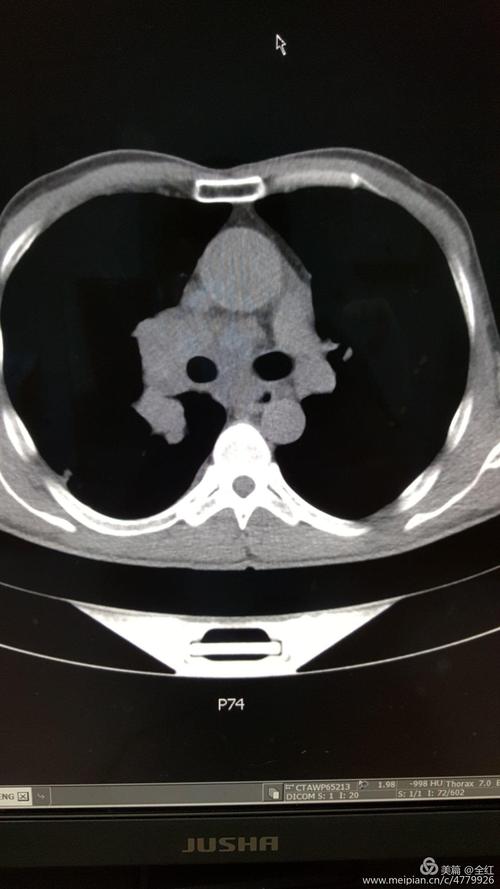

ct4228158f胸片示主动脉弓增宽主动脉瘤未排除纵

看片诊病之典型急诊胸片分享

ct11996f75y腹腔异常占位请专家会诊

冯xx男51岁五官科诊咽炎,咳嗽行胸片常规检查,发现右下肺占位,ct同诊